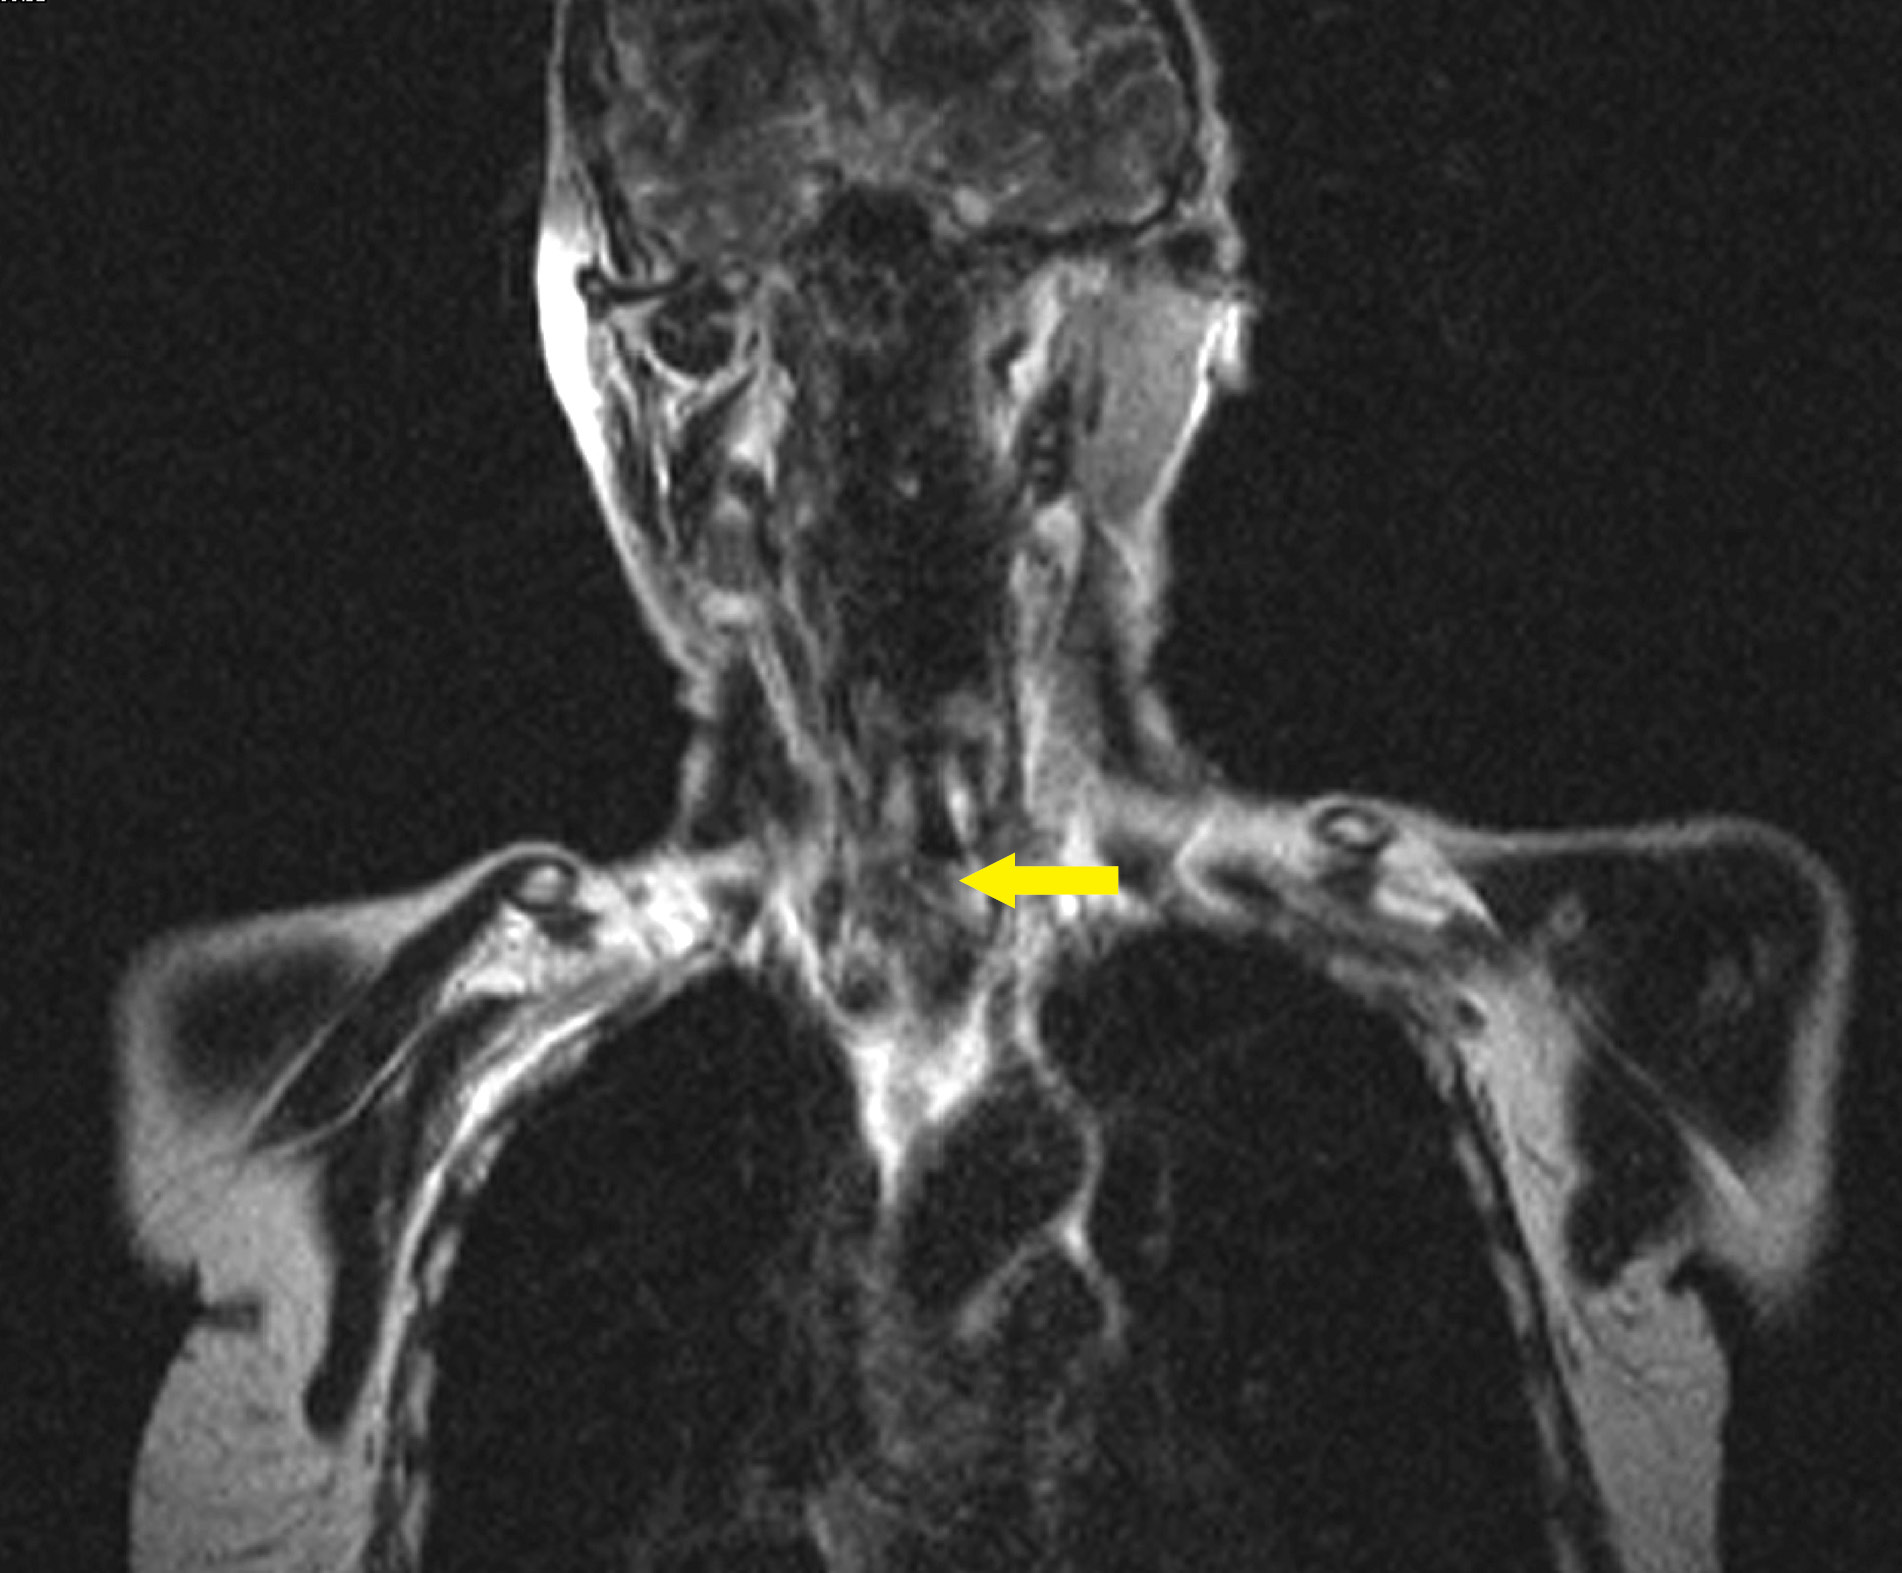

1. Рисунок 1. Пациент С. Рецидив рака щитовидной железы. Врастает в трахею и перстневидный хрящ. | |